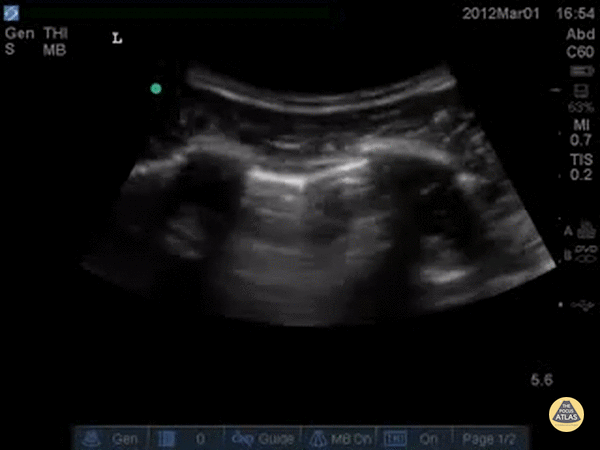

Pulmonary - Pneumothorax Lung Point

Decreased lung slide is highly sensitive, it lacks specificity. Lung point however, is a highly specific finding indicating a pneumothorax. Lung point indicates the transition point between normal pleura with normal lung sliding and where there is air disrupting the pleural space with decreased lung sliding. In this intercostal space, one can see lung with normal lung slide on the left, and decreased lung slide on the right, and a point where the lung slide changes, which is moving with inspiration. This is the lung point. Dr. Justin Bowra et al.